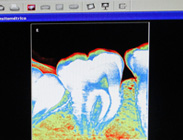

Endodoncia

En el consultorio tratamos las afecciones de la pulpa dentaria, más conocida como el “nervio” del diente.

Realizamos tratamientos de endodoncia (conducto) de forma convencional, manualmente con limas, así como también tratamientos de forma mecanizada, los cuales son de última tecnología y permiten simplificar los tiempos de trabajos, mejorando así el confort del paciente.

También, en endodoncia trabajamos bajo estrictas normas de bioseguridad, las cuales son imprescindibles para lograr el éxito en el tratamiento. De esta manera se logra sanear el interior del conducto radicular, dejándolo apto para la posterior rehabilitación del diente.